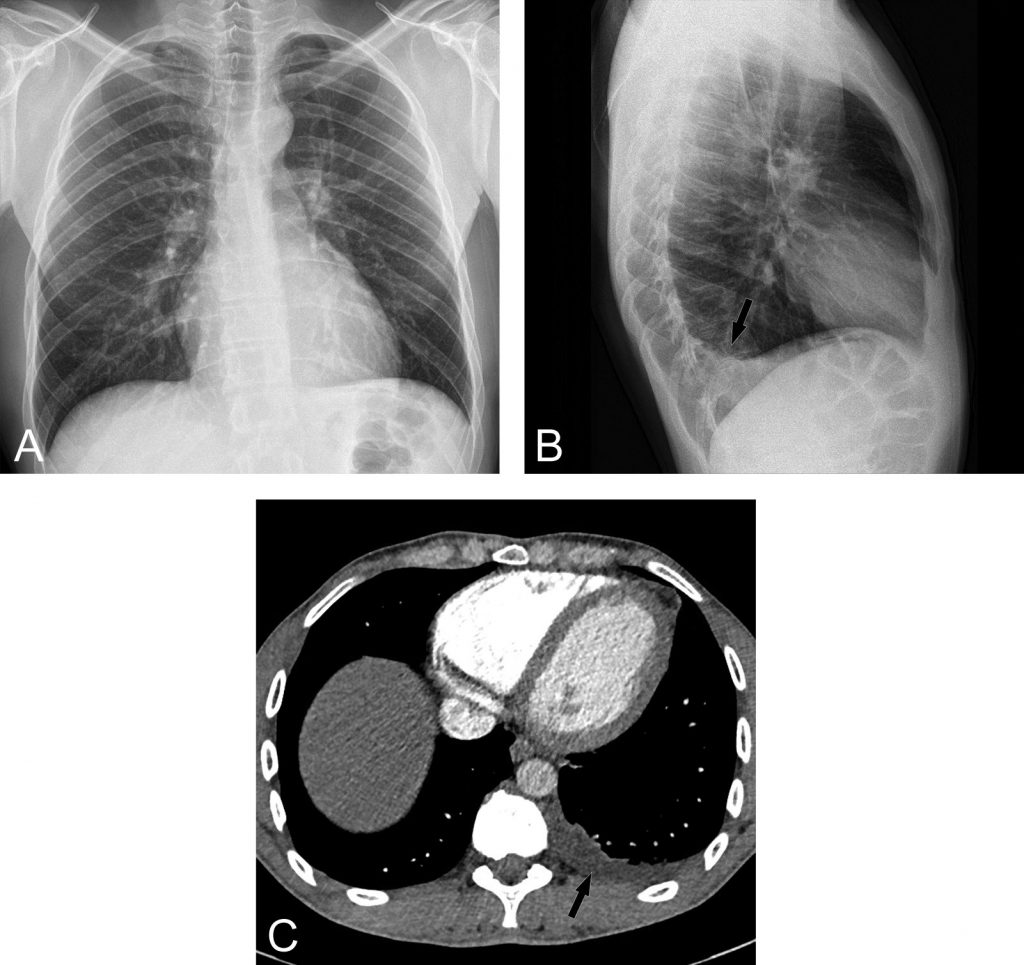

Fig. 91.4. Radiographies thoraciques et scanner d’un épanchement pleural gauche de faible abondance.

L’épanchement gauche n’est pas visible sur l’incidence de face (A), alors qu’il est bien visible sur l’incidence de profil qui est plus sensible pour les épanchements de faible abondance (flèche en B). Le scanner chez le même patient montre l’épanchement pleural gauche de faible abondance en situation postérieure (flèche en B).

Source : CERF, CNEBMN, 2022.